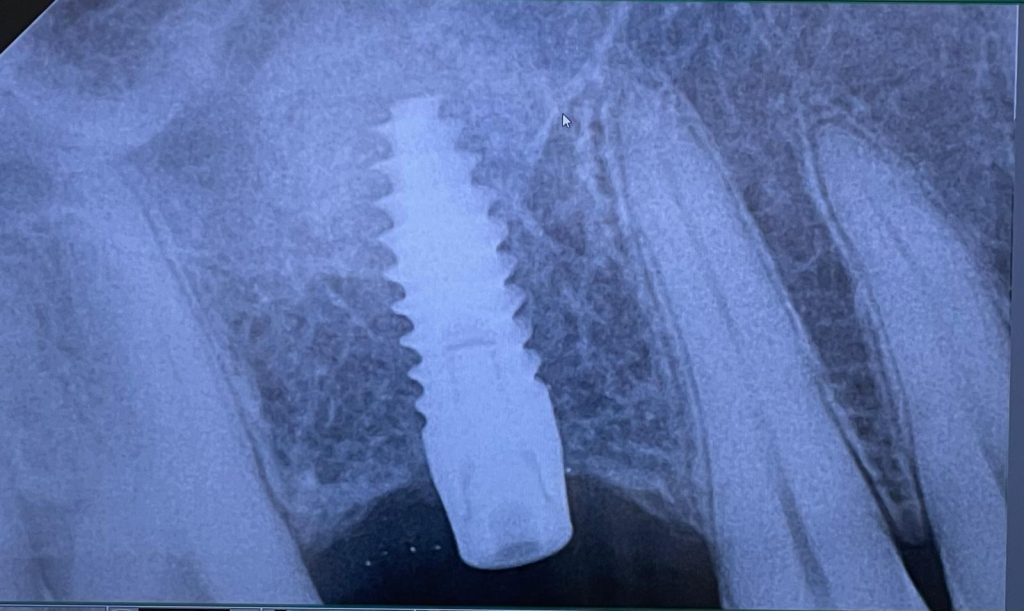

Eccoci con un altro caso del mese in cui vi mostro un intervento dove, data la presenza di una cresta residua insufficiente che non permetteva l’inserimento diretto di un impianto, è stato prima eseguito un mini rialzo di seno mascellare con tecnica MISE ed è possibile notare sopra l’apice dell’impianto un incremento di volume.